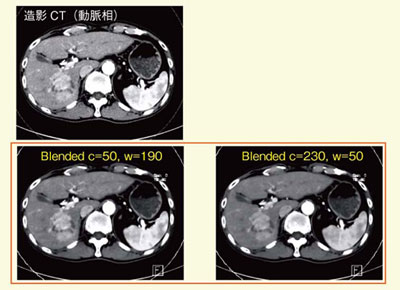

低管電圧画像は,造影コントラストは高いがノイズが多く,高管電圧画像は造影コントラストは低めだがノイズも少ない。これら両者を合成するcomposite imageにより,ノイズとコントラストのトレードオフの克服が期待できる。図11は,100kVと140kVの画像を種々の割合で合成したoptimum contrastで,多血性病変の濃染の見え方が変化している。このような微細な濃染の検出能の向上は,血流画像診断の精度向上につながるものと考えられる。

図11 composite image:optimum contrastの一例